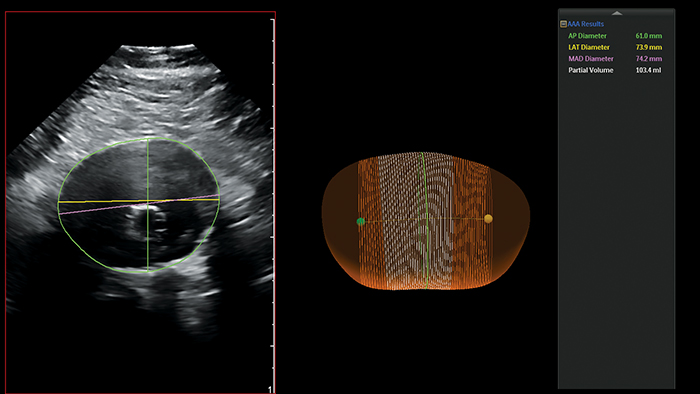

Philips AAA Model segments and quantifies 3D ultrasound data for use in surveillance of native and post-EVAR AAAs.

Philips AAA Model provides key measurements; including the maximum anterior-to-posterior (AP) diameter and partial volume, while also indicating the centerline of the aneurysm.

The maximal diameter of an AAA is ideally measured perpendicular to the centerline, a methodology that so far has only been feasible with 3D CT and magnetic resonance angiography (MRA)5. Philips AAA Model provides the centerline of the AAA throughout the volume of the 3D acquisition, making 3D ultrasound now also feasible with this methodology.

Philips AAA Model also provides the partial volume of the aneurysm which is beneficial as it has been observed that more than one-third of small AAAs, considered to be stable based on diameter alone, were actually growing in volume6.